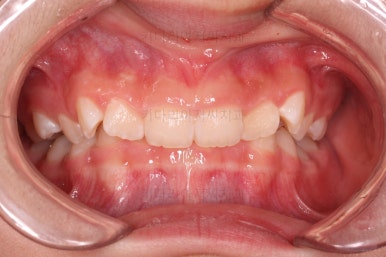

초진 시 입안의 모습입니다.

오른쪽 상단 사진을 보시면 어금니의 높이와 앞니의 높이의 차이가 많이 나요.

앞니가 솟구쳐 있는 양상인데요.

그 이유 때문에 어금니로 다물었을 때 위아래 앞니가 많이 겹쳐서 아래 앞니가 아예 보이지 않는 상황이었어요.

이를 "과개교합"이라고 표현합니다.

그리고 전반적으로 아래 치열이 윗니에 비해 뒤로 밀려 있어서, 어금니의 맞물림이 좋지 못하고 듬성듬성해 보이는 상황이었어요.